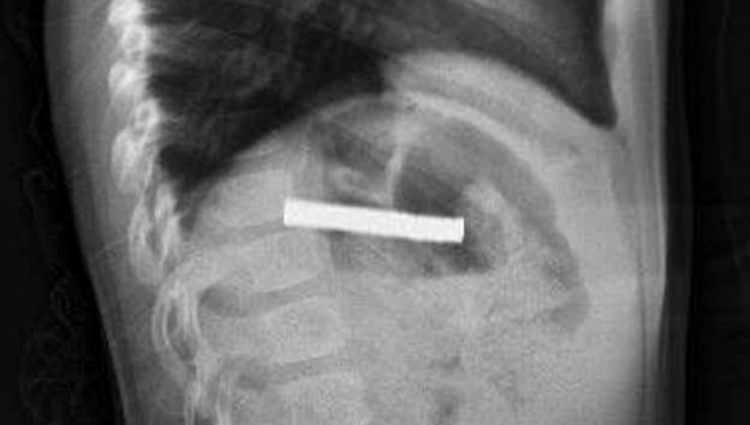

Midesinden 19 mıknatıs çıkarılan çocuk doktorları şoke etti!

Elazığ’da 3 yaşındaki bir çocuk, rahatsızlanması üzerine hastaneye kaldırıldı. Çocuğun yuttuğu 19 mıknatıs, Fırat Üniversitesi Hastanesi'nde başarılı bir operasyon ile çıkartıldı.

Edinilen bilgiye göre, Erzurum’da bir çocuk evde bulunan 19 tane mıknatısı yuttu.